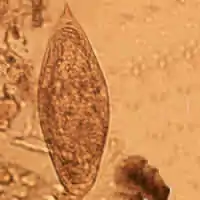

La característica clínicamente definitoria de la mayoría de las especies de esquistosoma es el tamaño y la forma de sus huevos. Los huevos de Schistosoma intercalatum tienen una espina terminal y tienden a ser moderadamente más grandes que los de S. haematobium (aproximadamente 130 × 75 μm). El origen del nombre 'intercalatum' proviene de la observación de que sus huevos son de un rango intermedio entre S. haematobium más pequeño y S. bovis más grande. [2] Estos huevos son únicos porque se tiñen de rojo cuando se los expone a la técnica de Ziehl-Neelsen, lo que ayuda a la identificación. [3] Cuando se observa utilizando microscopía electrónica de barrido, se puede observar que la superficie de S. intercalatum tiene una cantidad mucho menor de elevaciones tegumentarias, o protuberancias, que S. mansoni. Esta característica es consistente con la apariencia del tegumento de otros esquistosomas con espinas terminales.